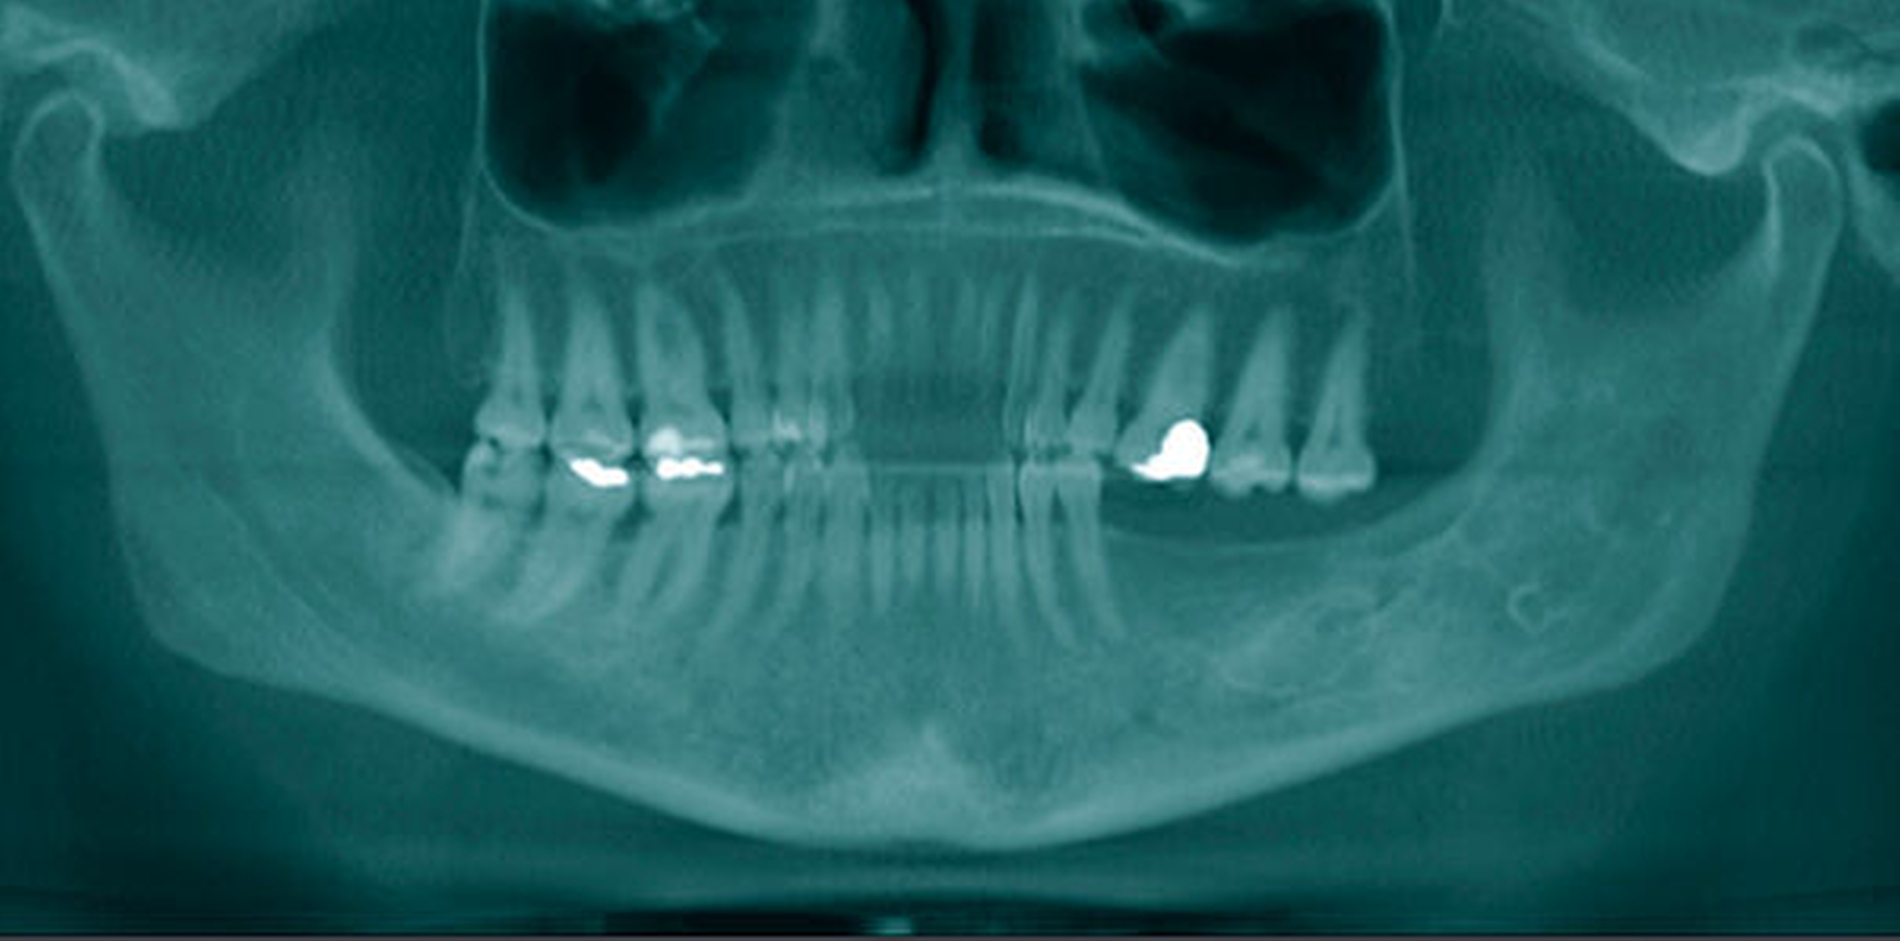

Aufgrund der tiefen intraossären Lage ohne direkten Zahnbezug oder andere klare Orientierungspunkte wurde zur gezielten Ansteuerung auf Basis des DVT-Datensatzes eine Osteotomie-Schablone 3-D-gedruckt (Material: MED 610, Drucker: EDEN 260V, Stratasys), die den Osteotomiezugang genau verschlüsselte (Abbildung 3a). Intraoperativ konnte dadurch die Keratozyste gezielt entfernt werden, ohne dass eine großflächige Osteotomie notwendig war oder ein erhöhtes Risiko für die Verletzung des N. alveolaris inferior bestand (Abbildung 3b). Der Befund wurde zystekotomiert und die Knochenhöhle zusätzlich ausgefräst (Abbildung 4). Auch die postoperative radiologische Kontrolle bestätigte eine optimale Lage der Osteotomie (Abbildung 5). Die postoperative Heilung war unproblematisch, drei Jahre nach dem Eingriff ist die Patientin rezidivfrei (Abbildung 6).